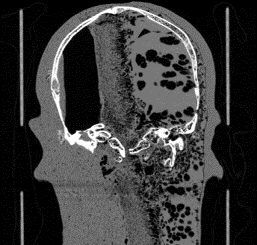

These CT slices are of the Case 0102 phantom cranium. Views were selected form the transverse, coronal, and sagital planes.